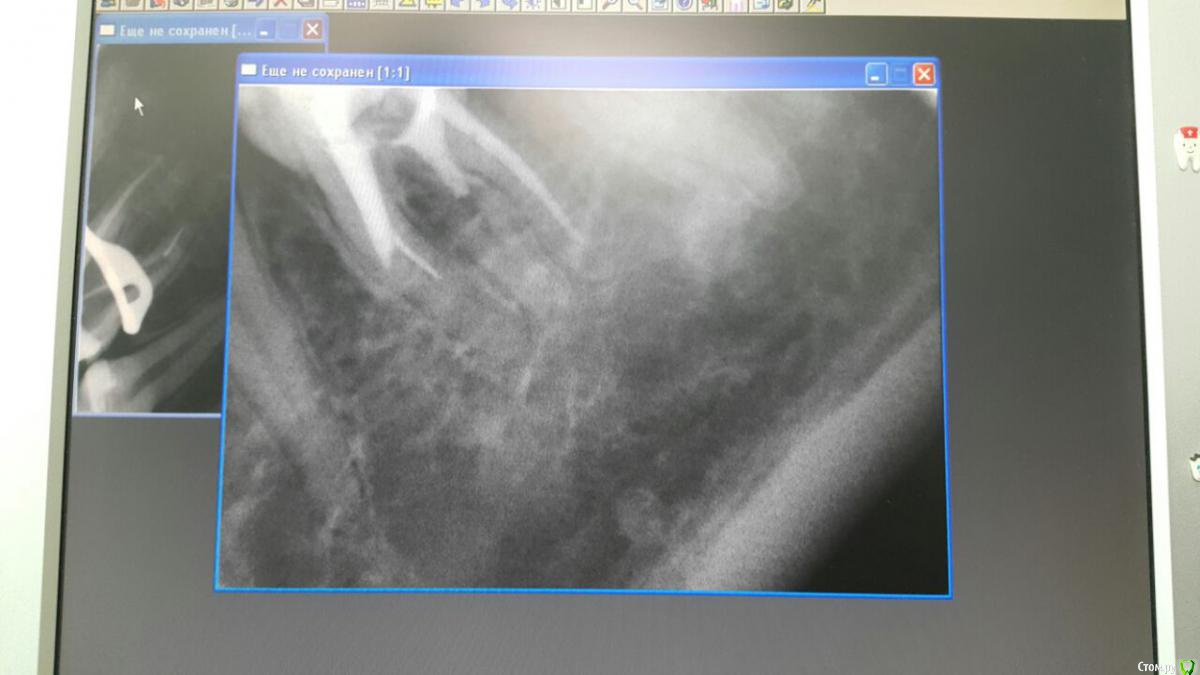

Анна Л Опубликовано 2 мая, 2018 Поделиться Опубликовано 2 мая, 2018 (изменено) Первый раз в 2016 году лечили мне зуб с пломбировкой каналов. Снимок номер 1. Неделю назад переплобмировали мне каналы, врач оставила там интсрумент. Снимок тоже прилагаю. Направила к доктору лечить под микроскопом. Он не смог достать интсрумент и сказал что не прошел все каналы, это невозможно и сделал все что мог и залил каналы горячей гуттаперча и врменной пломбой. Через 3 для пошла на процедуру подгтовие вкладки, снова временная пломба. И вот на след день у меня начал ныть зуб,температура 37, немного опухла щека, ночью сплю зуб не беспокоит, а вот днем все та же ноющая боль и боль как будто до уха доходит. Пью третий день порошок Нимесил, 2 раза в сутки. Боль моя и не увеличивается и не ументшается. Врач говорит дальше пить Нимесил.Первый раз в 2016 году лечили мне зуб с пломбировкой каналов. Снимок номер 1. Неделю назад переплобмировали мне каналы, врач оставила там интсрумент. Снимок тоже прилагаю. Направила к доктору лечить под микроскопом. Он не смог достать интсрумент и сказал что не прошел все каналы, это невозможно и сделал все что мог и залил каналы горячей гуттаперча и врменной пломбой. Через 3 для пошла на процедуру подгтовие вкладки, снова временная пломба. И вот на след день у меня начал ныть зуб,температура 37, немного опухла щека, ночью сплю зуб не беспокоит, а вот днем все та же ноющая боль и боль как будто до уха доходит. Пью третий день порошок Нимесил, 2 раза в сутки. Боль моя и не увеличивается и не ументшается. Врач говорит дальше пить Нимесил. Изменено 2 мая, 2018 пользователем Анна Л Ссылка на комментарий